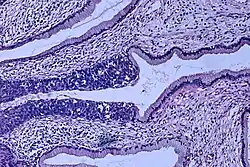

The naming and histologic classification of cervical carcinoma precursor lesions has changed many times over the 20th century. The World Health Organization classification system was descriptive of the lesions, naming them mild, moderate, or severe dysplasia or carcinoma in situ (CIS).[68][69] The term cervical intraepithelial neoplasia (CIN) was developed to place emphasis on the spectrum of abnormality in these lesions and to help standardize treatment.[69] For premalignant dysplastic changes, cervical intraepithelial neoplasia grading (CIN 1–3) is used. It classifies mild dysplasia as CIN1, moderate dysplasia as CIN2, and severe dysplasia and CIS as CIN3.[70] More recently, CIN2 and CIN3 have been combined into CIN2/3. These results are what a pathologist might report from a biopsy.

Invasive squamous cell carcinoma of the cervix is characterized by infiltration as irregular anastomosing nests or single cells.[75] This case is poorly differentiated. H&E stain. -

Invasive cervical squamous cell carcinoma on H&E histopathology and Ki-67 immunohistochemistry. The latter correlates well with the degree and level of dysplasia.[77] -